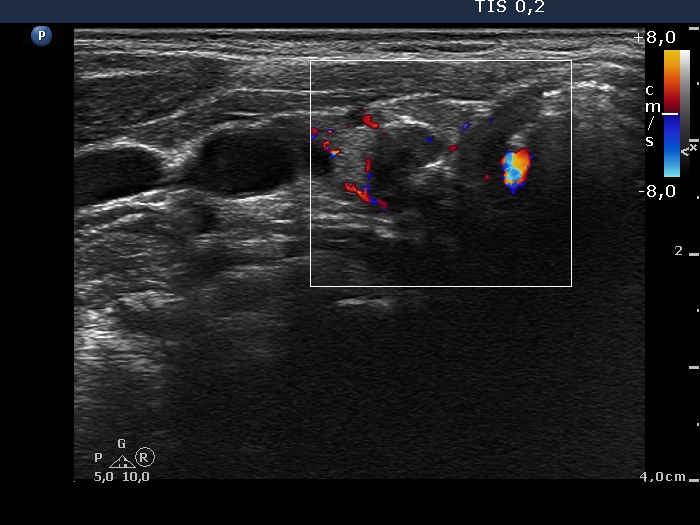

Study on 100 consecutive patients with thyroid nodule - case 022 (ultrasonographic picture 7)

Lower part of the right lobe, transverse view, color Doppler mode. This nodule does not show blood flow.